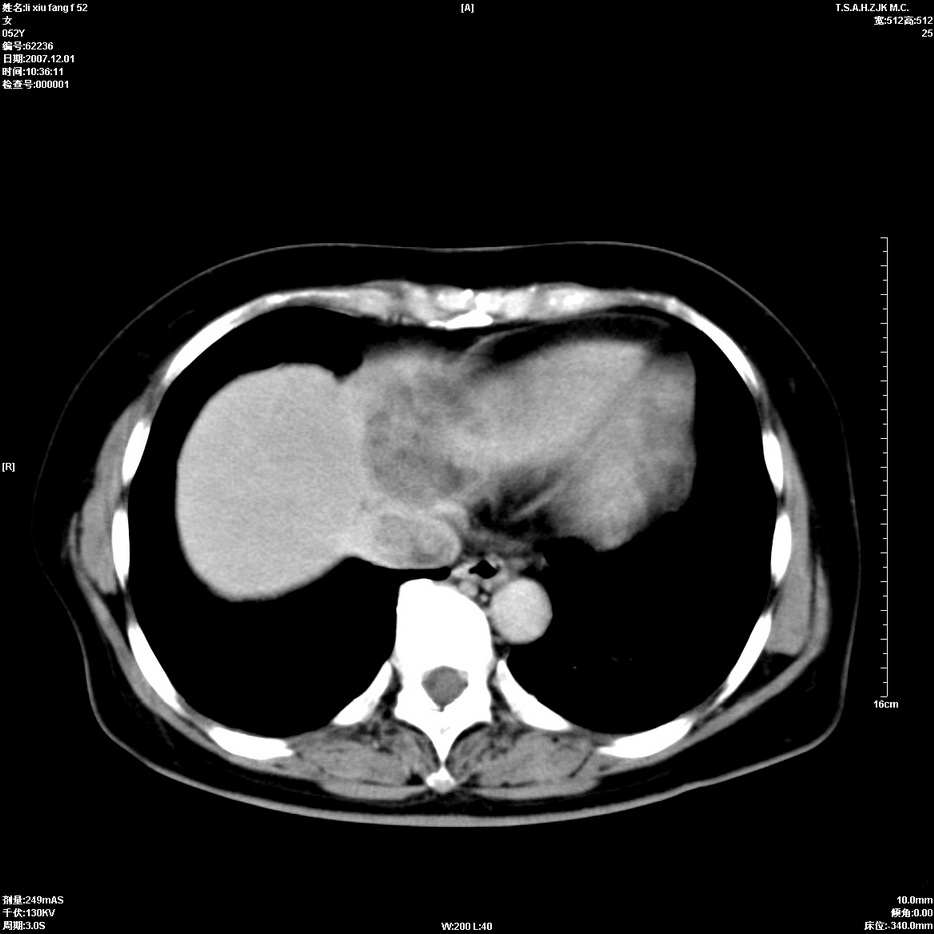

标题: CT12858:女,52岁,胎甲球蛋白861肝左叶占位,肝癌。下腔静 [打印本页]

标题: CT12858:女,52岁,胎甲球蛋白861肝左叶占位,肝癌。下腔静

肝左叶巨大低密度灶肿块,增强符合快进快出表现,有动静脉交通支;静脉期,下腔静脉内有充盈缺损,afp明显升高,支持肝癌并下腔静脉癌栓形成。

支持楼主   门静脉主干及左支癌栓形成

以下是引用拾荒者在2008-4-15 22:57:00的发言:[br]肝左叶巨大低密度灶肿块,增强符合快进快出表现,有动静脉交通支;静脉期,下腔静脉内有充盈缺损,afp明显升高,支持肝癌并下腔静脉癌栓形成。